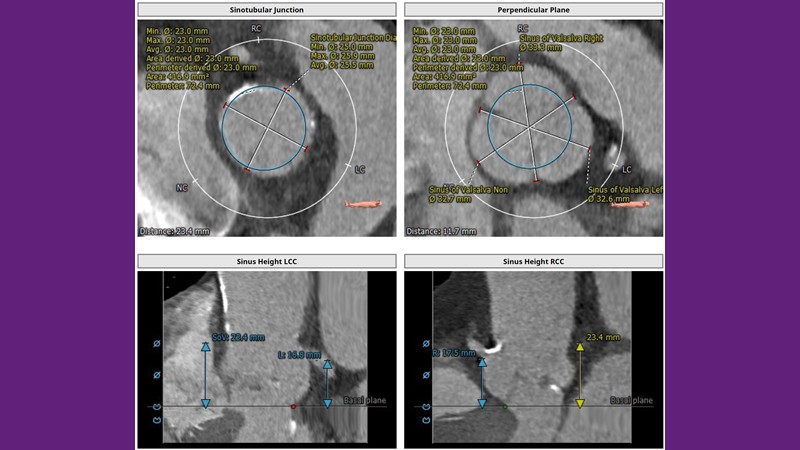

Don’t miss this PCR Tokyo Valves 2025 session replay, where leading experts share key techniques for simplifying and optimising TAVI procedures with the Evolut device. This session covers essential insights into safely performing procedures on patients with various anatomical types using the self-expandable valve, while emphasising the importance of long-term patient care and outcomes. Discover valuable strategies for surgical explantation of transcatheter aortic bioprostheses, coronary cannulation, and commissural alignment post-TAVR. Learn expert tips for streamlining procedures, such as semi-rapid pacing, using Dryseal long, and skipping pre-BAV to improve TAVI results. Watch now to stay ahead in the field!